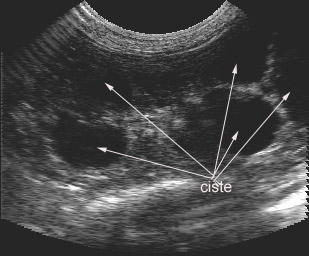

Ultrazvočni posnetek ledvičnih cist pri mački: